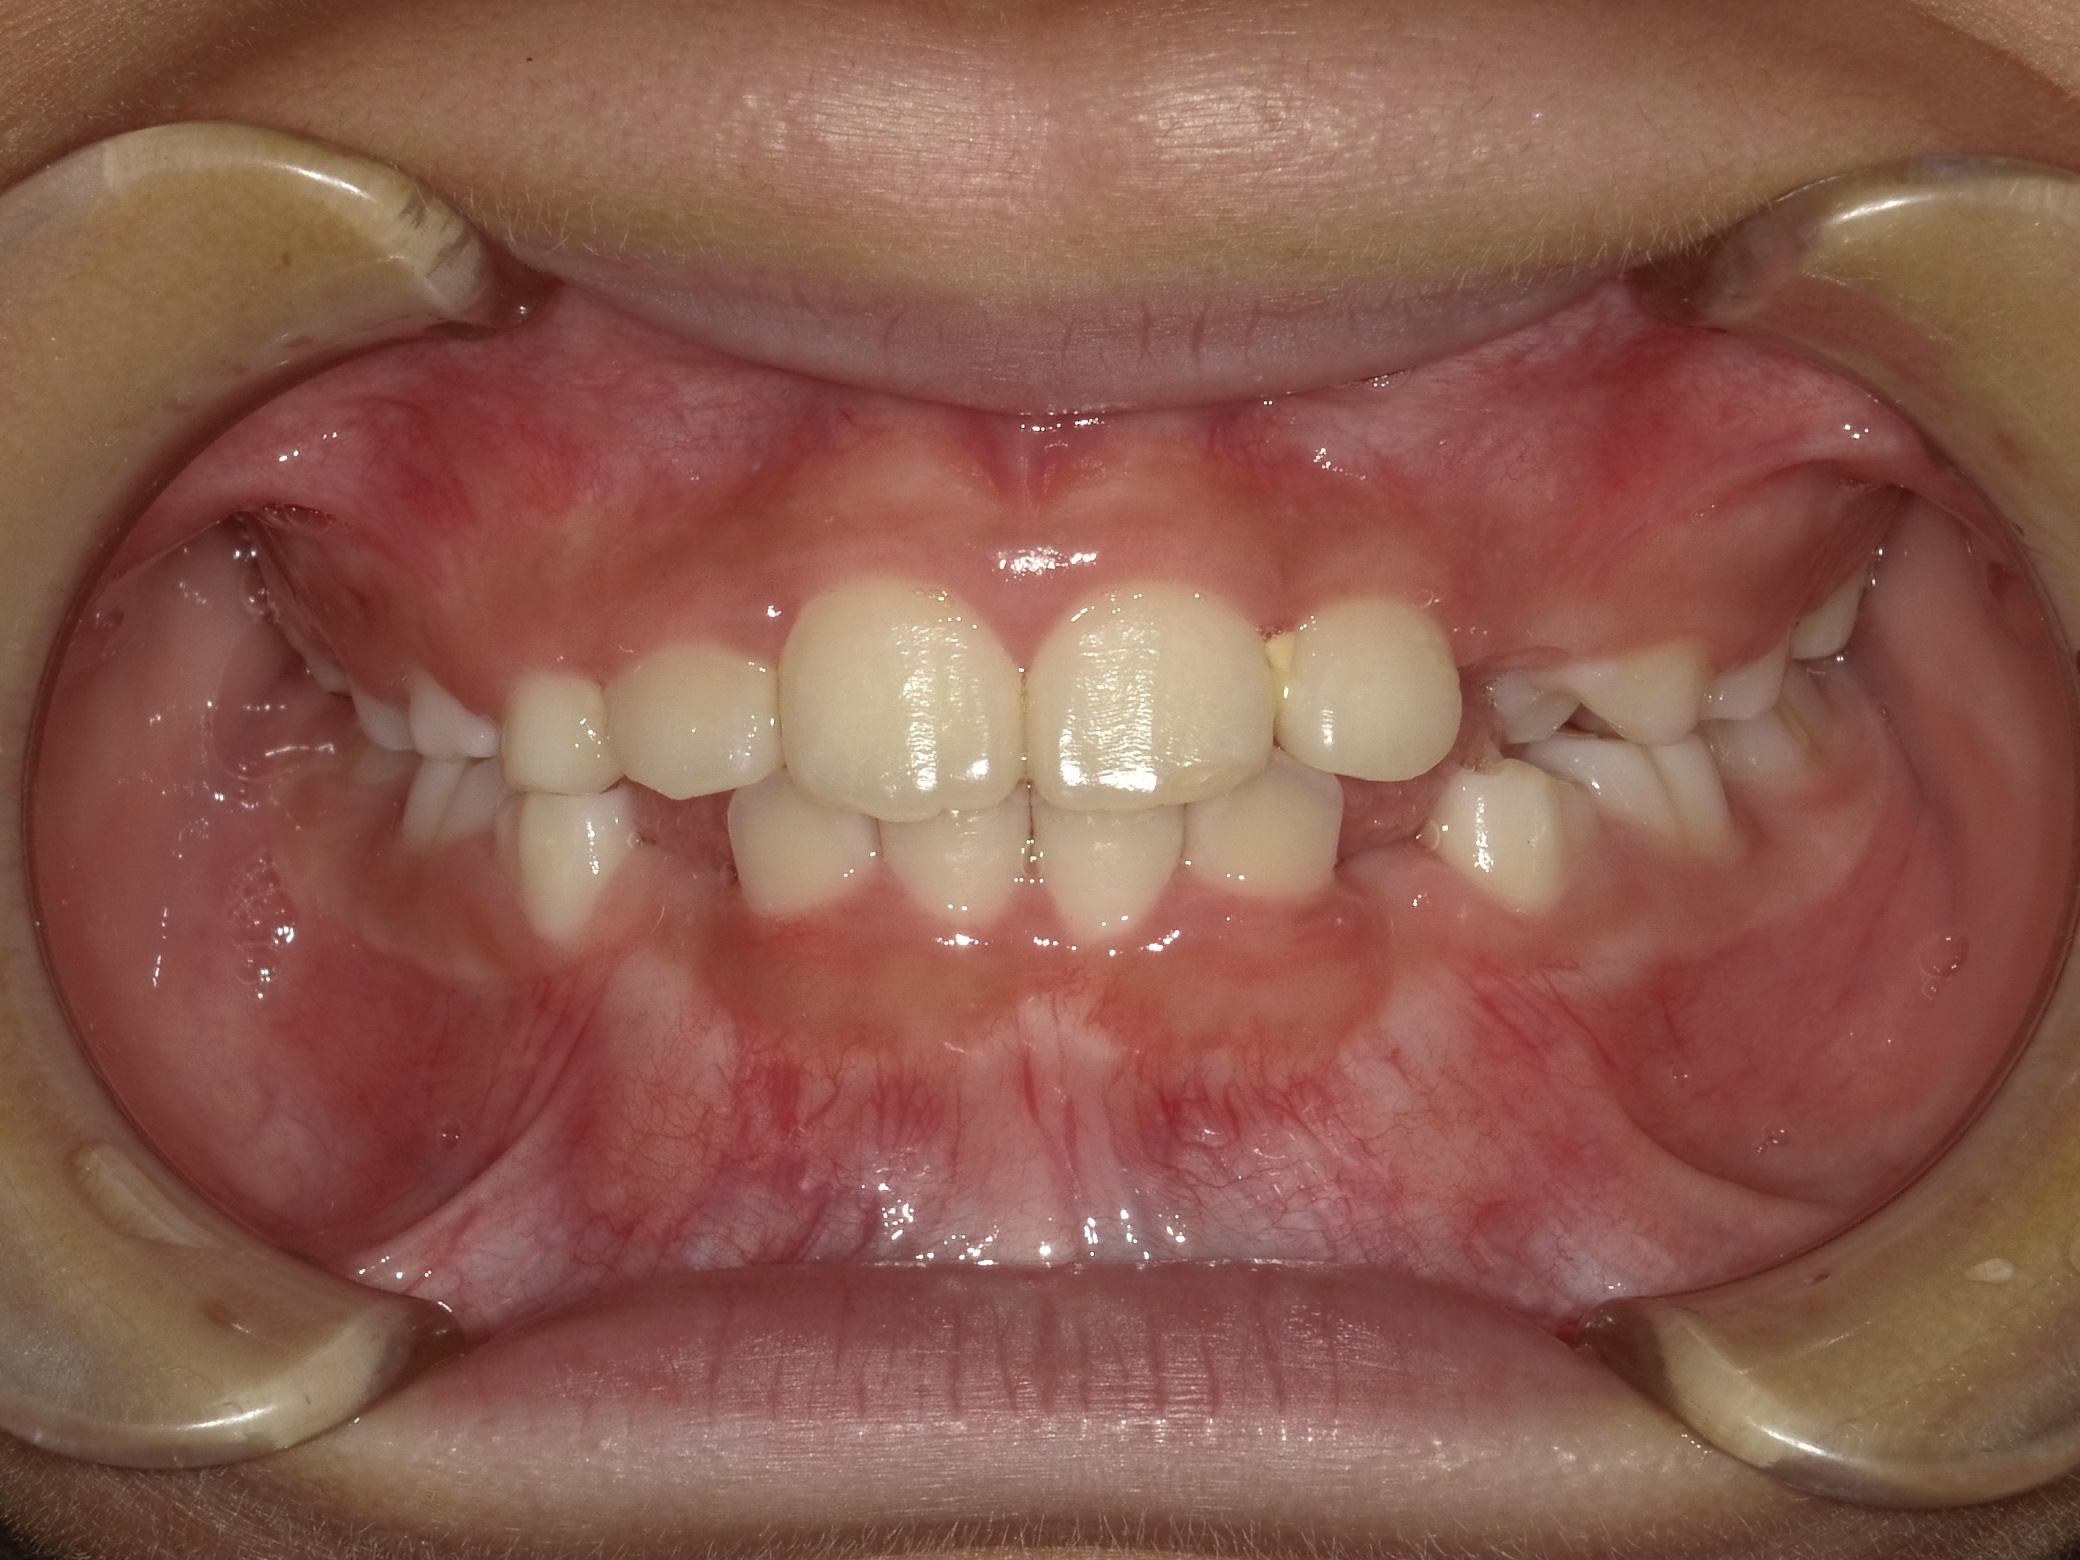

正面

| 治療内容 | インビザライン・ファースト |

| 治療詳細 | スペース不足や交叉咬合を整えるために、歯の表面にアタッチメント(白い突起)をつけ、治療を行いました。 |

| 患者情報 | 9歳 男性 予防矯正から移行 |

| 主訴 | 永久歯は生えそろう十分なスペースがない 一部分だけかみ合わせが反対 |